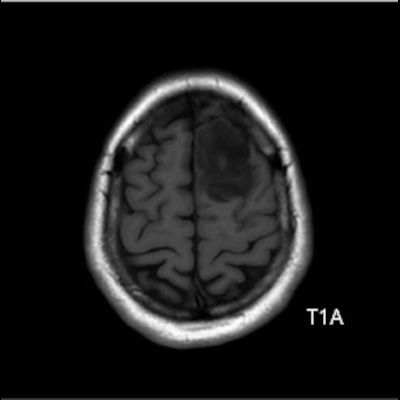

- Sol frontal kortikal-subkortikal yerleşimli aksiyel T2A görüntüde hiperintens sinyal özelliği gösteren (oklar) ve FLAIR görüntüde sinyali ağırlıklı olarak baskılanan (oklar) kitlesel lezyon izleniyor. Lezyon T1A görüntüde hipointens olup post-kontrast T1A görüntüde bu düzeyde patolojik kontrastlanma izlenmiyor (oklar).

- T1AG’de genellikle hipointens, T2AG’de ise genellikle homojen hiperintens görünümde ve kitle etkisi hafif-orta düzeydedir.Ödem genellikle eşlik etmez ya da minimal düzeydedir.

- Grade 2 ve 3 tümörlerde çoğunlukla kontrast tutulumu yoktur veya minimal düzeydedir. Grade 4 IDH-mutant astrositomlarda, nekroz veya mikrovasküler proliferasyon varsa heterojen kontrast tutulum gözlenebilir. Kontrast tutulumu her zaman malignite derecesini yansıtmayabilir; bu nedenle biyopsi ve moleküler analiz mutlaka gereklidir.